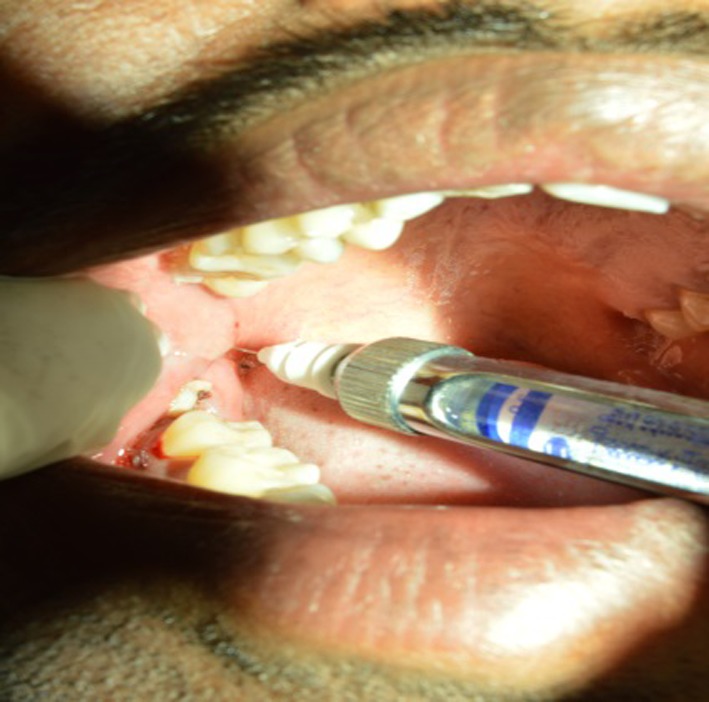

Systemically, healthy patients aged between 18 and 55 years were included in the study. Patients allergic to local anesthetic agent, smokers, alcoholics and pregnant patients were excluded from the study. These patients were divided into three groups. The principal investigator, who recorded the outcome measures for all the subjects, was unaware about the intervention received by each subject. After obtaining the informed consent, the patients recruited in the study were allotted to three groups in a sequential manner. The distribution of patients was done based on computer-generated chart given by statistician. Each group received mandibular anesthesia by a different technique, namely the inferior alveolar technique (Group A) (Fig. 1), Vazirani Akinosi technique (Group B) (Fig. 2) and Gow Gates technique (Group C) (Fig. 3). The anesthesia administration of all three techniques was done by second investigator. The principal investigator and the patient were unaware of the technique administered ensuring double blindness of the study. The procedures which were included in the study were normal extractions of the mandibular premolars, canines and incisors in the lower arch.

Fig. 1.

Depicting the administration of conventional inferior alveolar nerve block technique